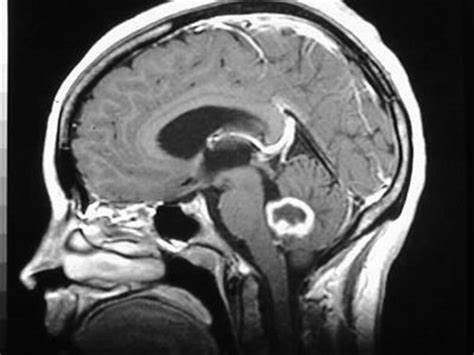

丘脑占神经轴的体积不到2%,故该部位起源的肿瘤较少,占颅内肿瘤的1%-5%,丘脑肿瘤以胶质瘤多见且以低级别为主。由于位置深在且毗邻重要功能区,其治疗一...

颅内胶质瘤有哪些症状? 颅内胶质瘤占位效应可引起头痛、呕吐、眼底视乳头水肿等症状和表现。大脑半球的胶质瘤可引起精神症状,如人格变化和记忆丧...